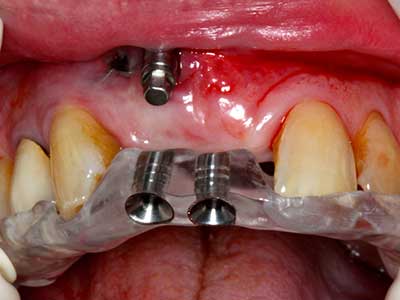

When surgical procedures are performed on bone in the immediate vicinity of sensitive structures such as blood vessels or nerves, rotary instruments pose a significant risk of iatrogenic injury. Piezoelectric devices can be helpful for preparation of bone covers and removal of hard tissue close to nerves, particularly for exposure of nerves after iatrogenic injury but also during nerve lateralization for resective and reconstructive procedures or implant placement (Fig. 17-20). Light contact between the piezotip and the nerve does not generally result in damage but proceeding incautiously with saw-like motions or attachments where a residual bone substrate remains may cause temporary or even permanent nerve damage. However, the risk of damage is considered to be substantially lower than when using saws or milling instruments (Pereira, Gealh et al. 2014).

As shown in the past, basically any bone surgery procedure represents a possible indication for piezo surgery. Thus preparation of the mobile segment in distraction osteogenesis (Fig. 23-25) and sandwich osteotomy uses special attachments without endangering the blood supply to the crestal section, which is essential for the success of both techniques (Gonzalez-Garcia, Diniz-Freitas et al. 2008).

For removal of an implant, a vestibular bone cover that is replaced after removal of the implant screw can be prepared to retain the contour of the alveolar ridge.